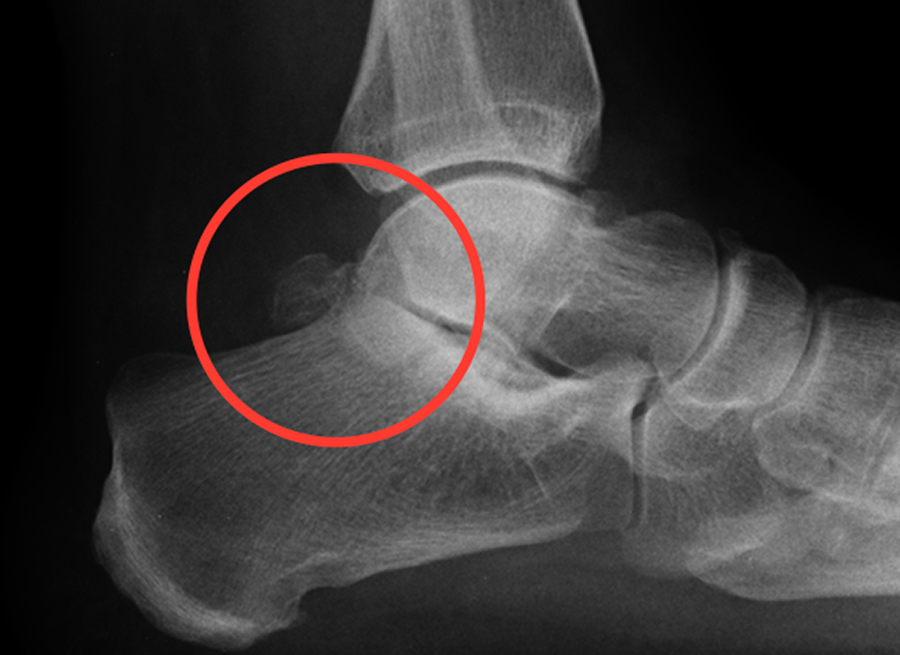

Os naviculare

Röntgenfoto van een accessoir os naviculare.

Dit kan hinderlijk zijn bij het dragen van schoenen. Verder kunnen er ook klachten ontstaan als het kraakbeen (of bindweefsel) tussen het accessoir os naviculare en het os naviculare (= scheepvormigbeen) beschadigd raakt. Dit geeft vooral klachten tijdens belasting van de voet. Vaak ontstaan er ook klachten door overbelasting, hierbij kun je denken aan overdruk door een foutieve voetstand.